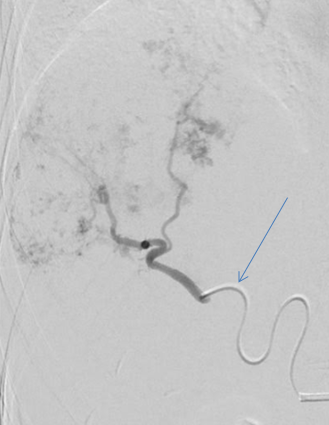

Embolisation For Liver Hemangiomas

Through a small prick in a thigh or arm blood vessels , catheters are tracked into the blood vessels feeding the hemangioma.

Treatment is administered into the haemangioma directly.